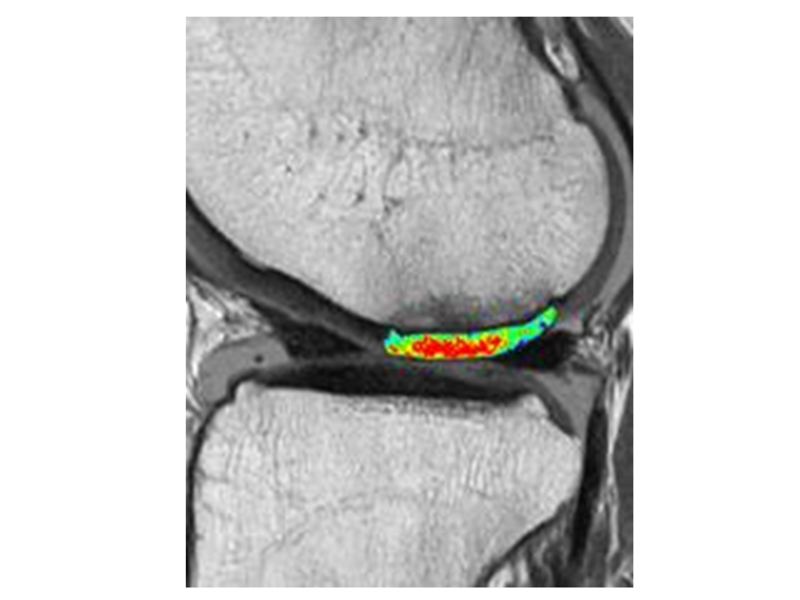

Nicht-invasive Knorpel-MR-Biomarker wie T2-, T2*- oder T1rho-Relaxationszeitmessungen sind in der Lage, frühe biochemische Knorpelmatrixveränderungen zu erkennen, vor allem Erhöhungen des Wassergehalts, Kollagenabbau und Verlust von Proteoglykanen. Es hat sich gezeigt, dass T2-Relaxationszeitmessungen das Fortschreiten des morphologischen Knorpelverlusts vorhersagen können, und sie können einen wichtigen Beitrag zur Beschreibung der Epidemiologie der frühen OA und zur Bewertung der Ergebnisse nach Knorpelreparaturverfahren leisten (Abbildung 1 und 2).